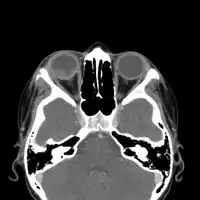

Imaging

CT chest: Paracoccidioidomycosis

CT chest: Paracoccidioidomycosis -

CT-scan head: Intraorbital enhancing mass lesion and two outer eyelid lesions with necrotic center and enhancing borders.

CT-scan head: Intraorbital enhancing mass lesion and two outer eyelid lesions with necrotic center and enhancing borders.